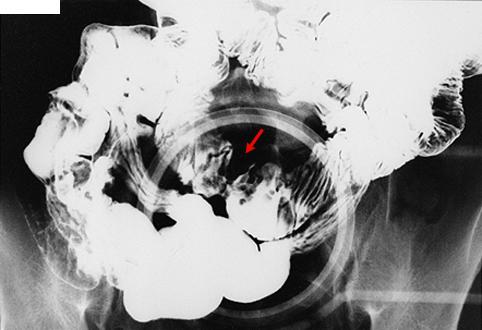

疾病(病理主体)的分类恶性淋巴系肿瘤/恶性淋巴瘤

部位(按器官分)小肠/空肠

检查方法X线

肿瘤最大直径35~40

肿瘤的深度s(a)